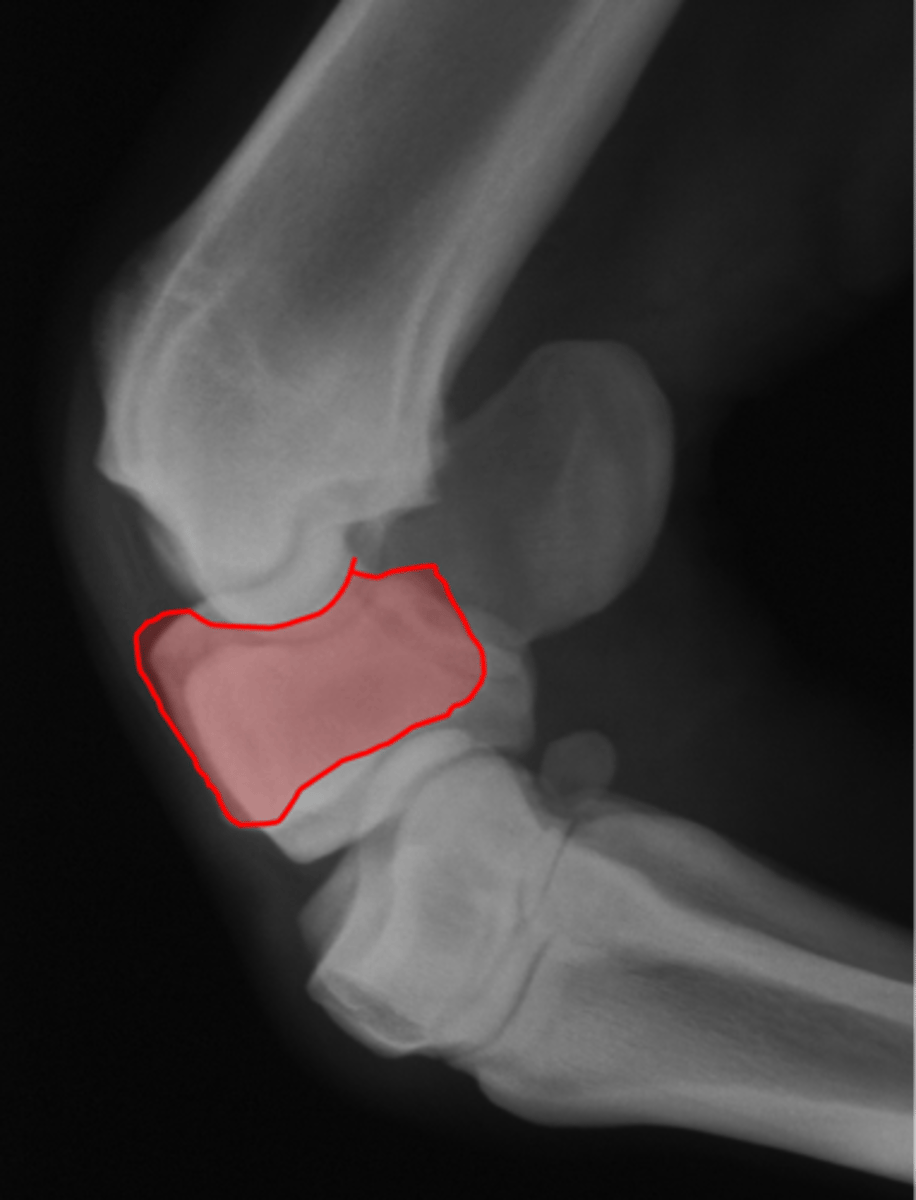

Fetlock joint, LM

ID joint and view

Fetlock joint, DP

ID joint and view

Fetlock joint, DLPMO/DMPLO

ID joint and view

Fetlock joint, flexed LM

ID joint and view

Proximal sesamoid bone

Sagittal ridge

Condyles of third metacarpal bone

Palmar process of P2

Proximal sesamoid bones

Sagittal ridge

Attachment of collateral ligaments

Proximal sesamoid bones

Palmar process of P1

Condyles of the third metacarpal bone